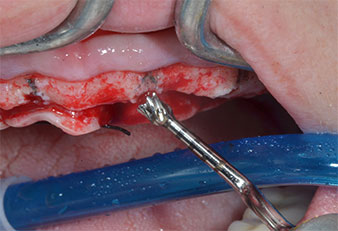

Compte tenu de la dureté relative de l’os (D2) à cet endroit, les sites recevant des implants de 10mm de long aux régions 11 et 21 ont été finalisés à l'aide d’une fraise de 4mm de diamètre, associée à un contre-angle chirurgical W&H WS-75 L, au moteur d'implantologie Implantmed de W&H ainsi qu’au module Osstell ISQ de W&H. En revanche, en raison de leur structure osseuse molle, les sites postérieurs ont été préparés en vue de l’obtention d’un diamètre final de 3mm à l'aide de l’insert Piezomed I3P. Les implants ont enfin été posés par voie transgingivale (Flap Less) pour obtenir l’ostéointégration dans un délai de trois mois (Figures 6-10). L'appareil existant a été maintenu sur quatre implants provisoires (Fig. 8).